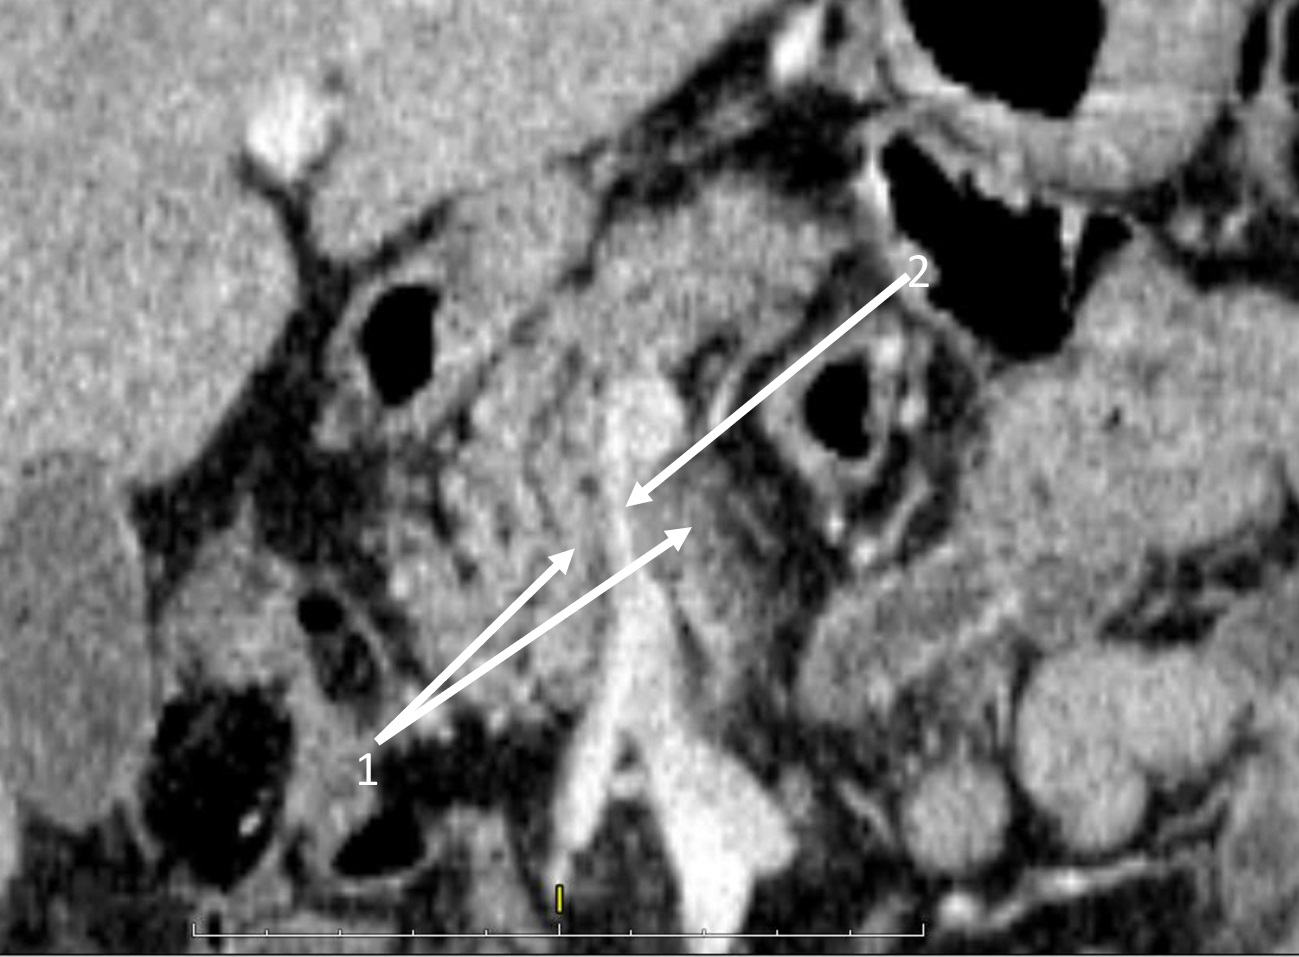

|  | 4. Состояние опухоли после 12 курсов FOLFIRINOX | |

| Тема | ||

| Тип | Исследовательские инструменты | |

|

Посмотреть

(261KB)

| Метаданные ▾ | |